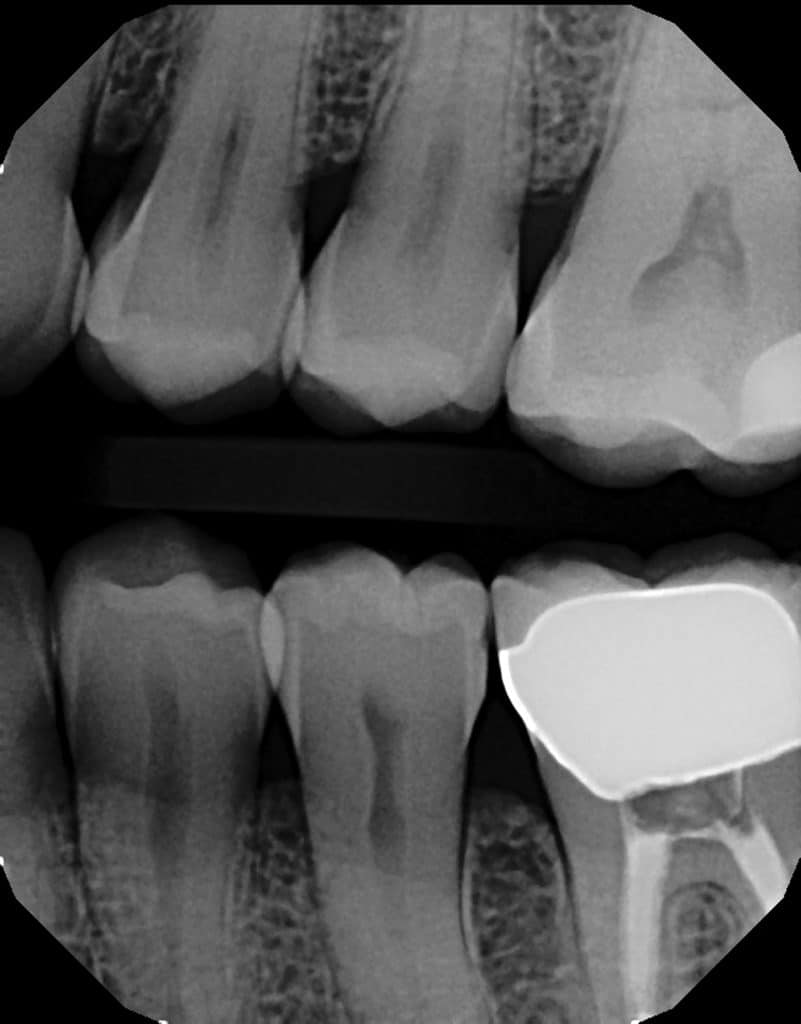

Bitewings reveal the presence and extent of decay in the back teeth, specifically in areas where. One bitewing is taken for each side to assess the posterior teeth. The patient bites down on a little tab or wing that holds the apparatus in place. Bitewing radiography is an efficient imaging method that can be. Bitewing radiographs take their name from the original technique which required the patient to bite on a small wing. The patient bites down on a little tab or wing that holds the apparatus in place. Generally, these x rays are taken once per year and are used to diagnose decay that is found in between the teeth and in new or recurring decay under existing.

Bitewing xray with cavities 2 Palms Dentist, Shirley Christchurch What Is A Bite Wing Generally, these x rays are taken once per year and are used to diagnose decay that is found in between the teeth and in new or recurring decay under existing. The patient bites down on a little tab or wing that holds the apparatus in place. Bitewing radiography is an efficient imaging method that can be. One bitewing is taken. What Is A Bite Wing.